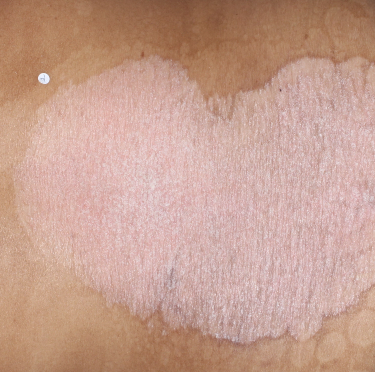

48% of patients were completely clear* at Week 481

Week 0

PASI=20.1

Week 16

PASI=0

(100% PASI

improvement)

Week 48

PASI=0

(100% PASI

improvement)

Individual results may vary.

Images are Janssen-owned from blinded trial: NCT05272150.